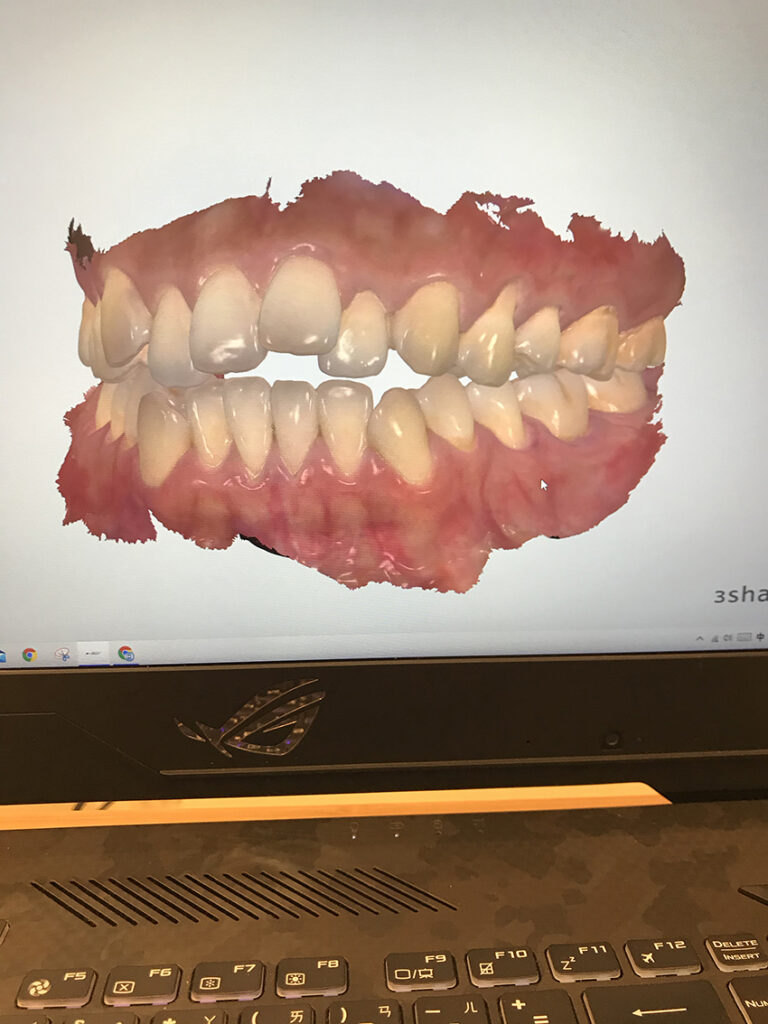

咬合部分:牙齒開咬矯正問題

Before:看看這個牙齒矯正前根本咬不斷任何東西的咬合XD

After:牙齒開咬的部分其實我原本不抱期待可以調整到完美,第一是因為我知道我自己口腔小(所以牙齒才很亂),以前小時候傳統牙套的牙齒矯正還曾經用擴張器把我的上顎撐開爭取空間,但依舊沒有解決。第二是因為我很珍惜我每一顆牙齒,加上臉型已經很窄了,所以堅持不拔牙,能調整的空間更有限。

因此這次SOV隱形矯正我想說能把牙齒排整齊就好,牙齒咬合就看緣分吧。但沒想到在聰哥的巧手和SOV隱形矯正的完美合作下,我的牙齒咬合竟然調整到最佳狀態。